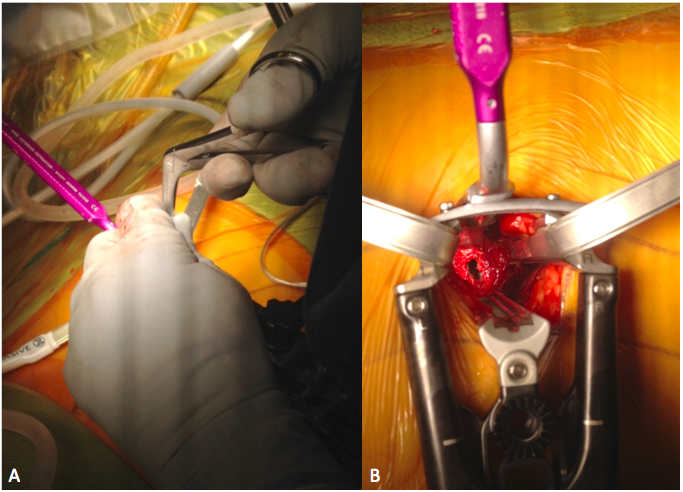

Descargas

6. Berjano P, Gautschi OP, Schils F, Tessitore E. Extreme lateral interbody fusion (XLIF®): how I do it. Acta Neurochir (Wien) 2015;157(3):547-51. doi: 10.1007/s00701-014-2248-9